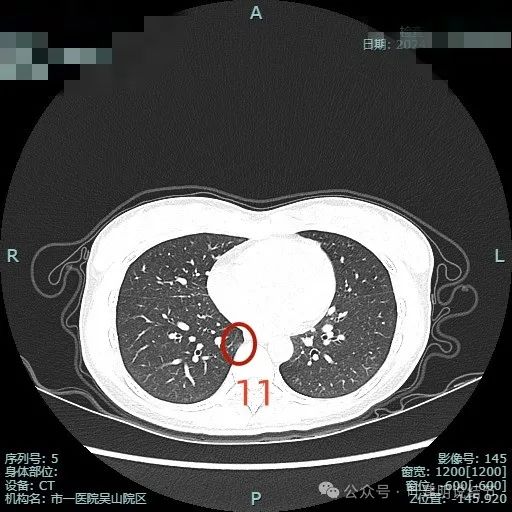

病灶11:右下叶近脊柱处淡磨玻璃结节,整体轮廓较清,考虑肺泡上皮增生可能大。